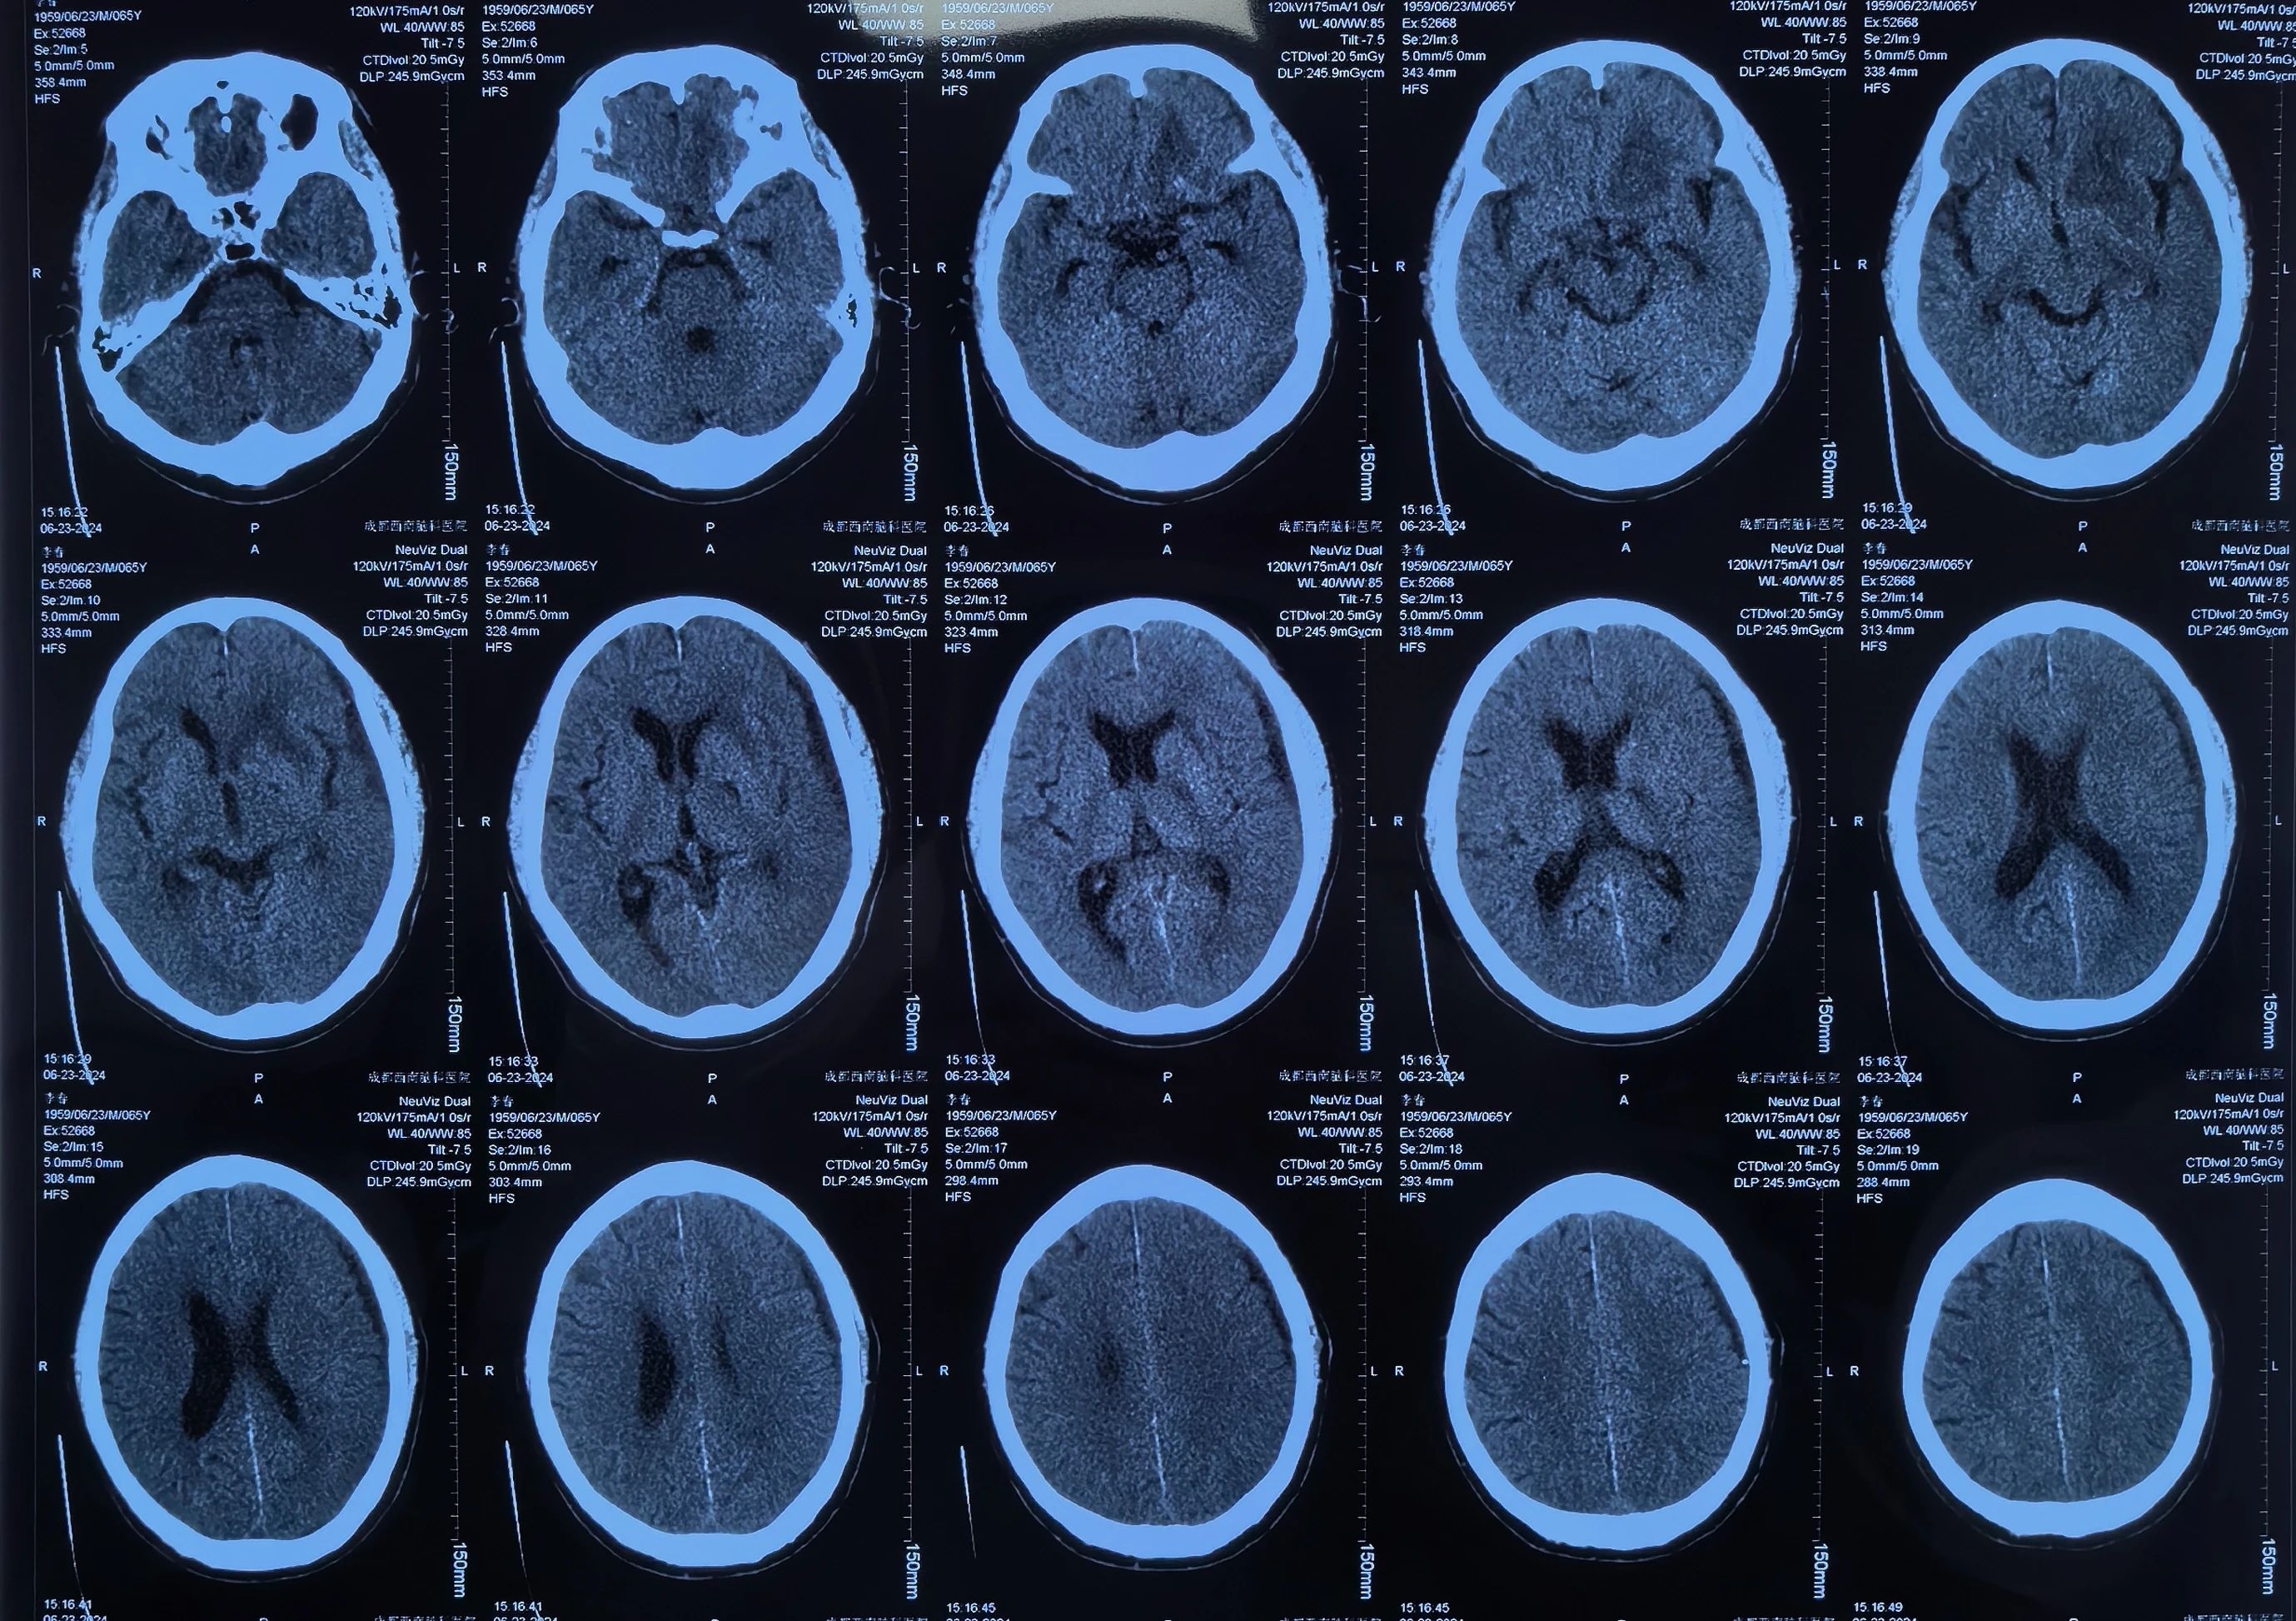

李先生手术后

术后李先生自觉头痛明显减轻,术后第三天复查头颅CT提示:硬膜下血肿基本清除,脑移位恢复正常。